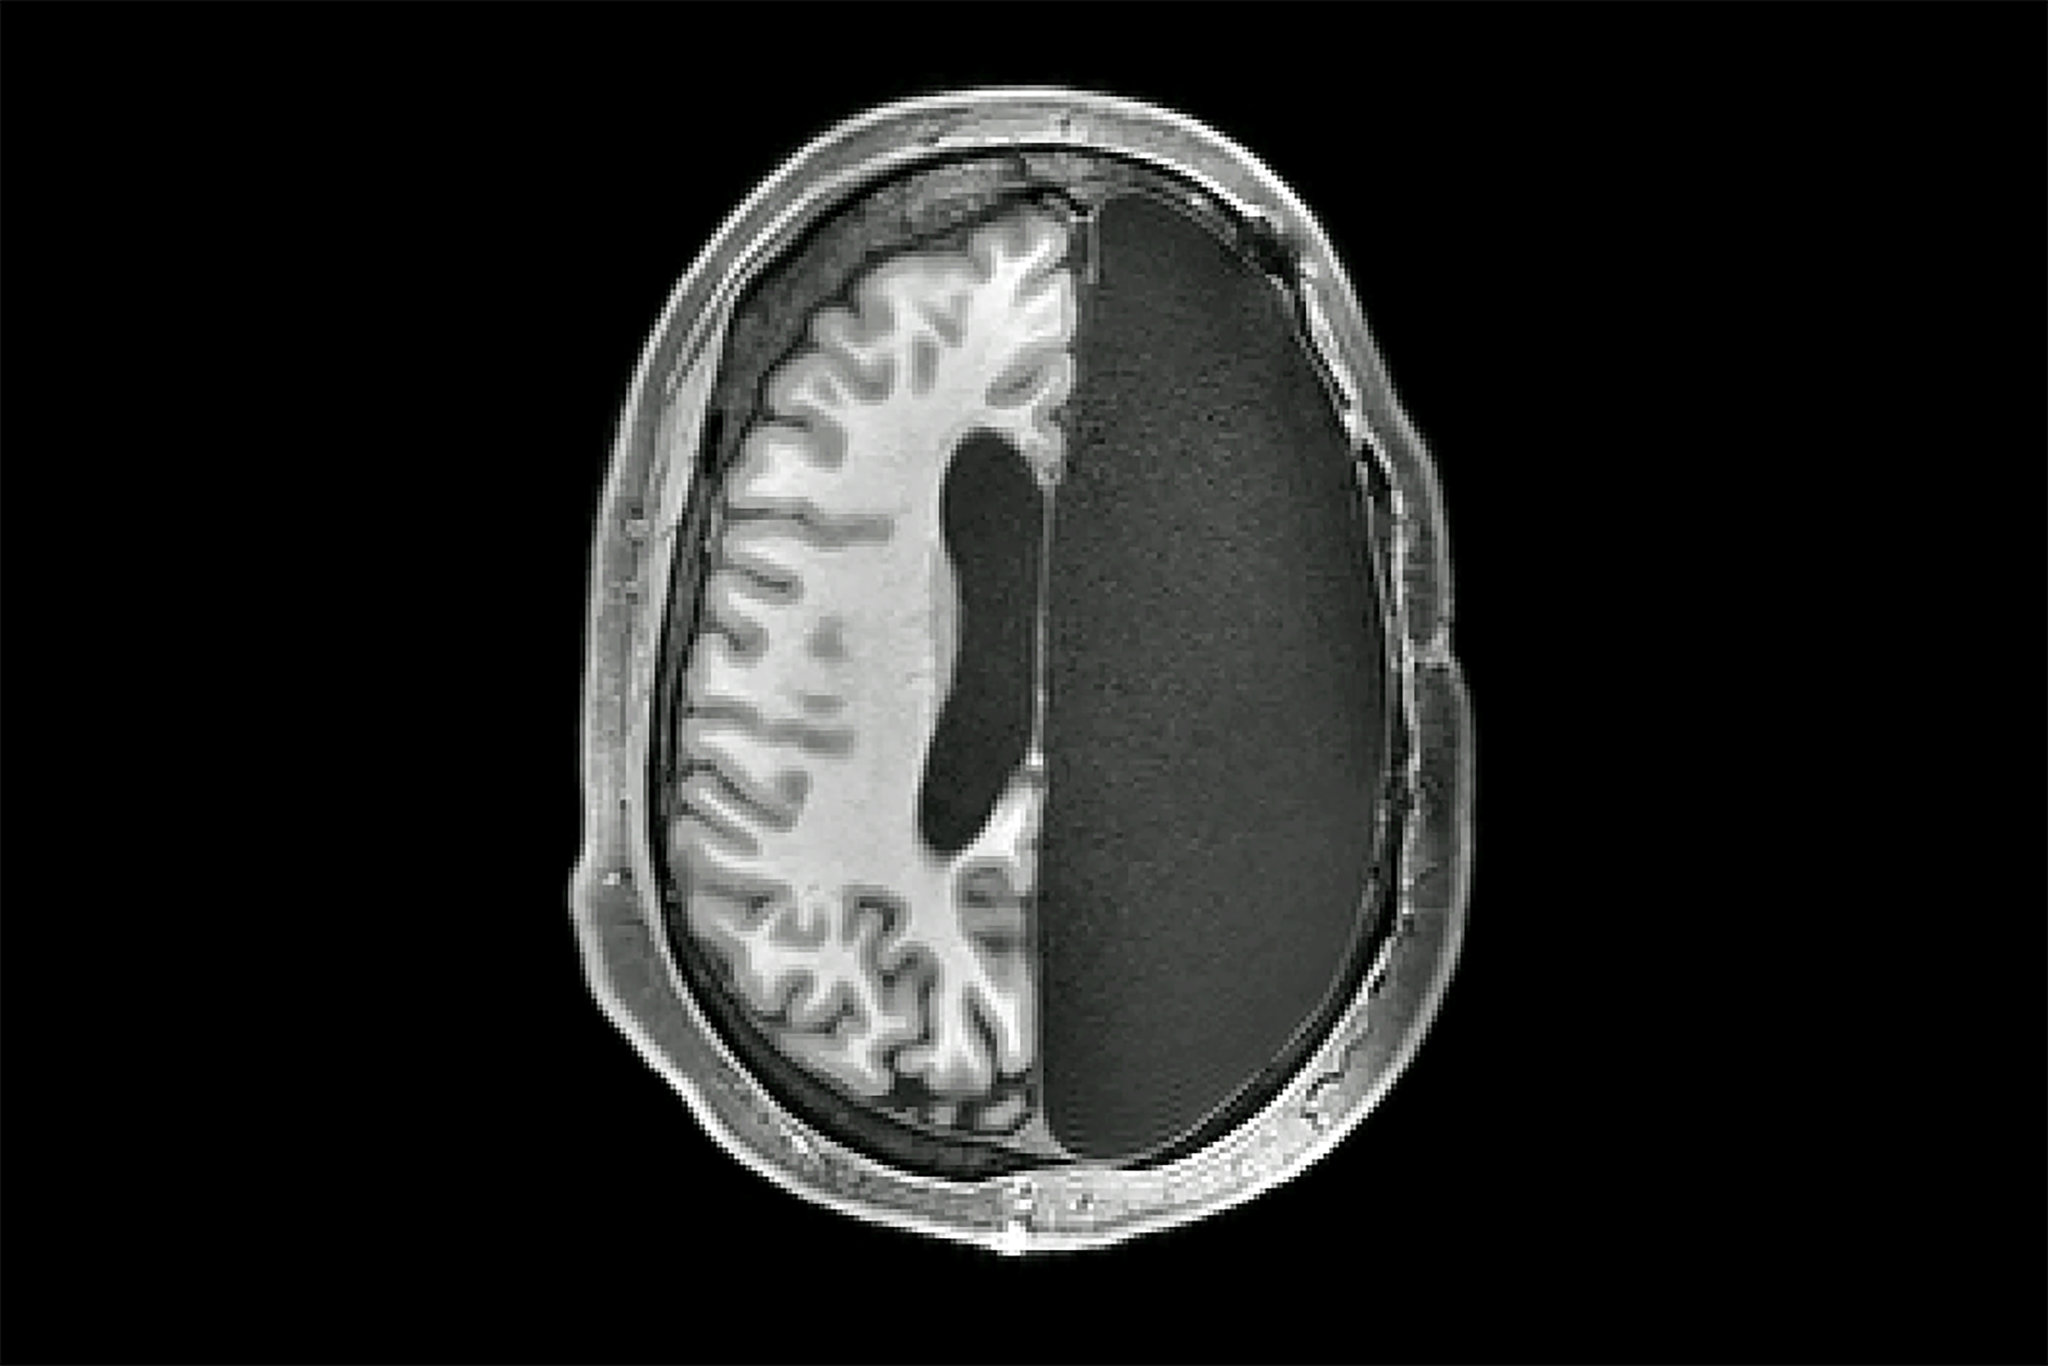

Is it confirmed that her personality and such is still intact? She can still speak without slurring and can recall information without (much) delay, and has complete motor skills? If so, that's absolutely miraculous. It's still a miracle she lived and has been recovering, it would just be unbelievable that she was able to make it without some form of permanent damage. Then again, she's still young, she'd be able to be more resilient than someone like Gabby Giffords who was shot in her 40s and whose speech never fully recovered.

I may not know much about the brain but I'm pretty sure that if a part of the brain is damaged, the human brain can compensate by increasing the function in the other hemisphere. People have had half of their brains surgically removed in childhood (anatomical hemispherectomy) to end their severe seizures, and manage to become seemingly normalish people. The human body is surprisingly both extremely strong and fragile at the same time

She should be entering phase 3 of TBI recovery which lasts 6-12 months following the injury where cognitive faculties can rapidly increase. Permanent sequelae injury will be obvious after recovery plateaus. Of course it being a focal and open brain injury makes recovery more likely but the swelling and skull removal may counteract that.

TBIs tend to leave permanent impairments to executive functioning but without knowing where the bullet hit it’s hard to know if that will be the case for her. Either way, with a proper care team and planning the potential for cognitive recovery can be quite high. I hope she has an excellent neuropsychologist on her team.